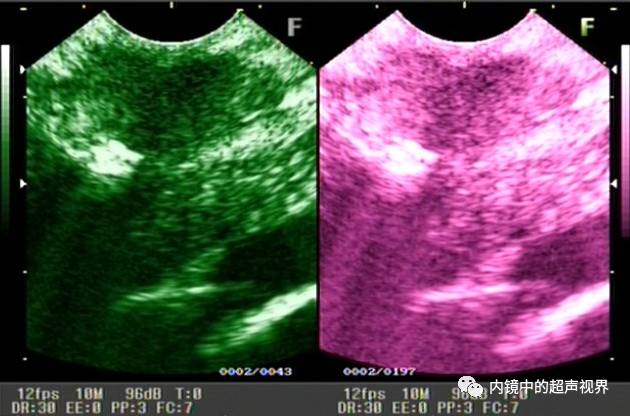

我现在使用的超声内镜DR可调节范围为30-90。以下三张图片显示的是同一个胰头肿物,肿物回声与胰腺回声非常接近,DR分别为90、70、40,其它参数相同,您更喜欢哪一张。

再说伪彩,它把黑白图像处理成黑橙、黑绿、黑蓝、黑粉等图像,一定程度上改变了图像的视感,类似于FICE、iSCAN等后处理光学染色功能,萝卜白菜各有所爱,喜欢哪个直接拿走。

胰头占位